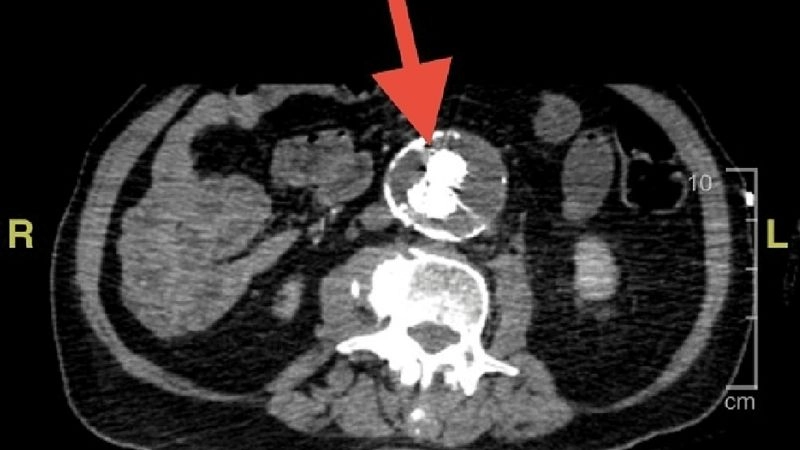

Aortitis diagnosis with advanced medical imaging

Aortic aneurysm as a complication of aortitis